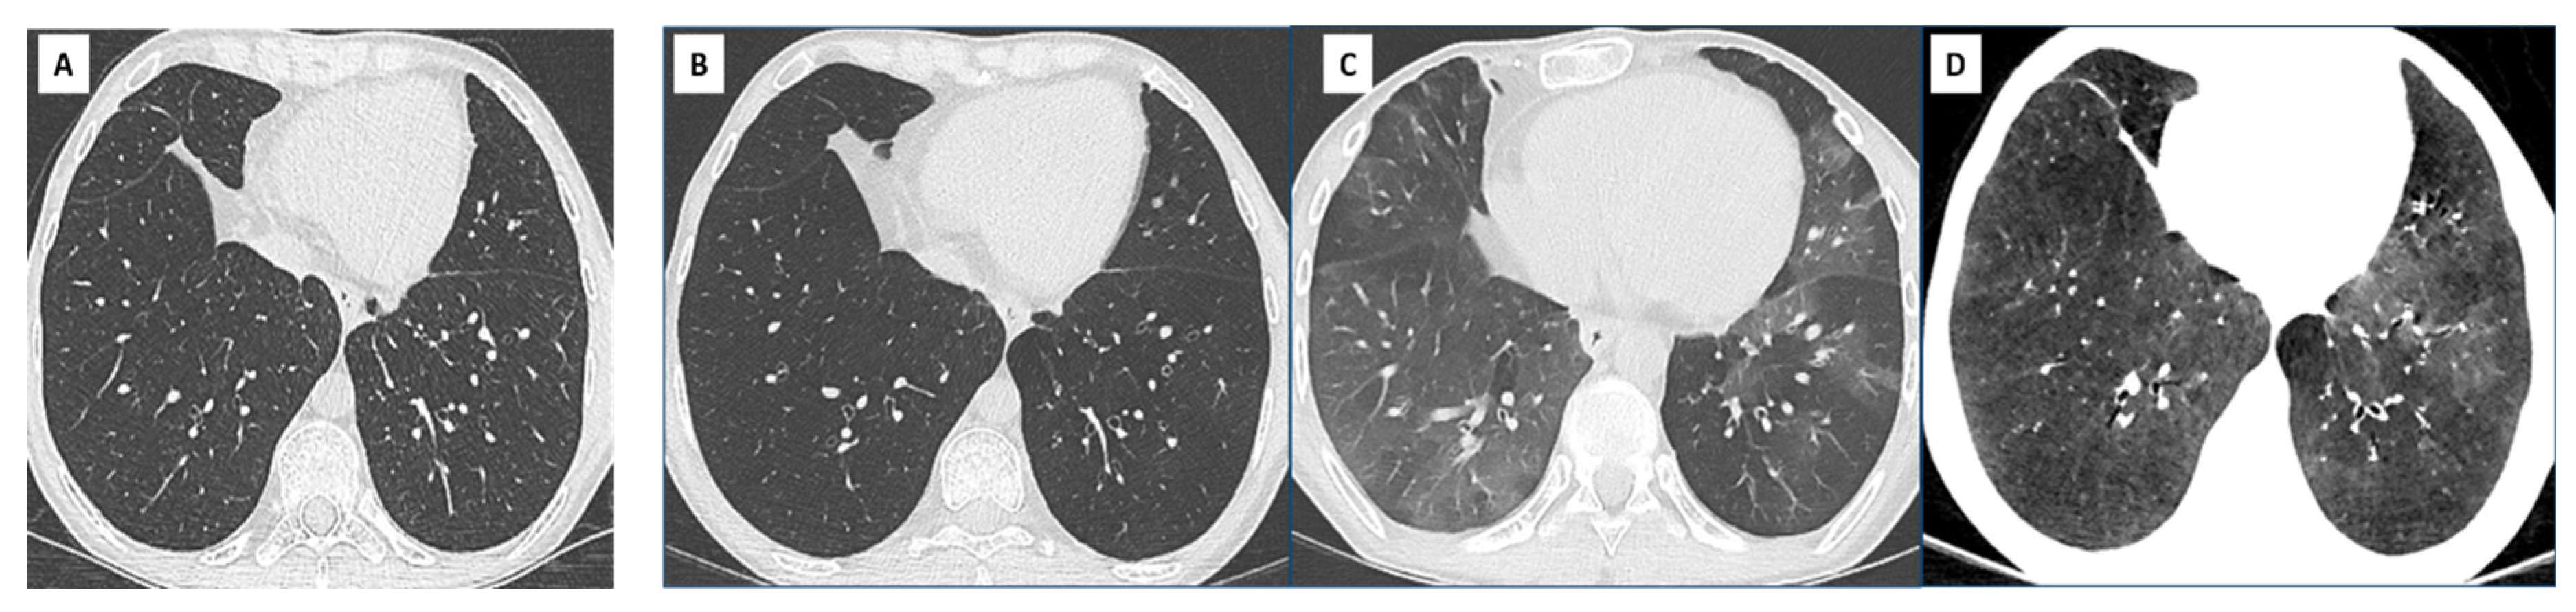

- Hota, P.; Dass, C.; Kumaran, M.; Simpson, S. High-resolution CT findings of obstructive phenotypes of chronic lung allograft dysfunction: More than just bronchiolitis oblierans syndrome. AJR Am. J. Roentgenol. 2018, 211, W13–W21. [Google Scholar] [CrossRef] [PubMed]

- Byrne, D.; Nador, R.G.; English, J.C.; Yee, J.; Levy, R.; Bergeron, C.; Swiston, J.R.; Mets, O.M.; Muller, N.L.; Bilawich, A.-M. Chronic Lung Allograft Dysfunction: Review of CT and Pathologic Findings. Radiol. Cardiothorac. Imaging 2021, 3, e200314. [Google Scholar] [CrossRef] [PubMed]

- Dettmer, S.; Shin, H.-O.; Vogel-Claussen, J.; Westphal, M.; Haverich, A.; Warnecke, G.; Welte, T.; Wacker, F.; Gottlieb, J.; Suhling, H. CT at onset of chronic lung allograft dysfunction in lung transplant patients predicts development of the restrictive phenotype and survival. Eur. J. Radiol. 2017, 94, 78–84. [Google Scholar] [CrossRef] [PubMed]

- Gazourian, L.; Ash, S.; Meserve, E.E.; Diaz, A.; Estepar, R.S.J.; El-Chemaly, S.Y.; Rosas, I.O.; Divo, M.; Fuhlbrigge, A.L.; Camp, P.C.; et al. Quantitative computed tomography assessment of bronchiolitis obliterans syndrome after lung transplantation. Clin. Transplant. 2017, 31, e12943. [Google Scholar] [CrossRef] [PubMed]

- Mortani Barbosa, E.J.; Shou, H.; Simpson, S.; Gee, J.; Tustison, N.; Lee, J.C. Quantitative computed tomography metrics from the transplanted lung can predict forced expiratory volume in the first second after lung transplantation. J. Thorac. Imaging 2018, 33, 112–123. [Google Scholar] [CrossRef] [PubMed]

- Mortani Barbosa, E.J.; Simpson, S.; Lee, J.C.; Tustison, N.; Gee, J.; Shou, H. Multivariate modeling using quantitative CT metrics may improve accuracy of diagnosis of bronchiolitis obliterans syndrome after lung transplantation. Comput. Biol. Med. 2017, 89, 275–281. [Google Scholar] [CrossRef] [PubMed]